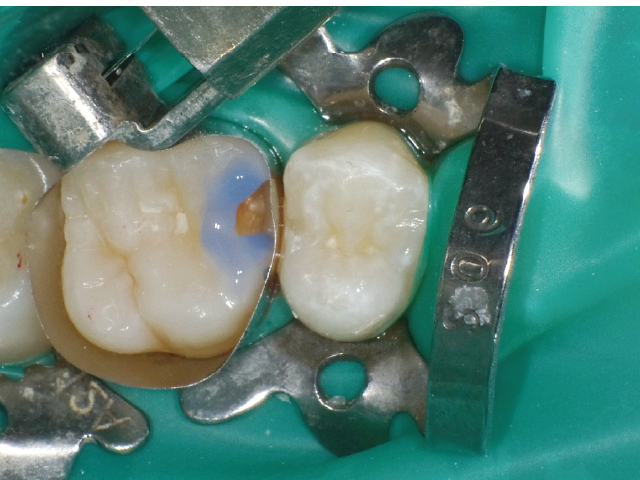

②充填段階(図10~22)

窩洞形成完了後は隣接面部健全歯質の残存範囲によりコンポジットレジンの充填時に用いるマトリックスシステムを選択していきますが、今回はシンプルな操作で設置可能なトッフルマイヤータイプのマトリックスシステムを選びました。隣在歯との距離が小さく、フラットな隣接面形態の再現が必要な症例には最適で、同時に精度の高い窩洞の防湿も可能です。使用したメタルのマトリックスバンドの厚さは30µmと非常に薄く、隣在歯との間に適切な接触関係を回復することができます。

接着操作には窩縁部エナメル質へのセレクティブエッチングに続いて、2ステップタイプのセルフエッチングシステム(クリアフィル® メガボンド®2 : クラレノリタケデンタル)を使用し、フロアブルレジンとペーストタイプレジンとを併用したシンプルな積層充填操作により隣接面形態を回復しました。